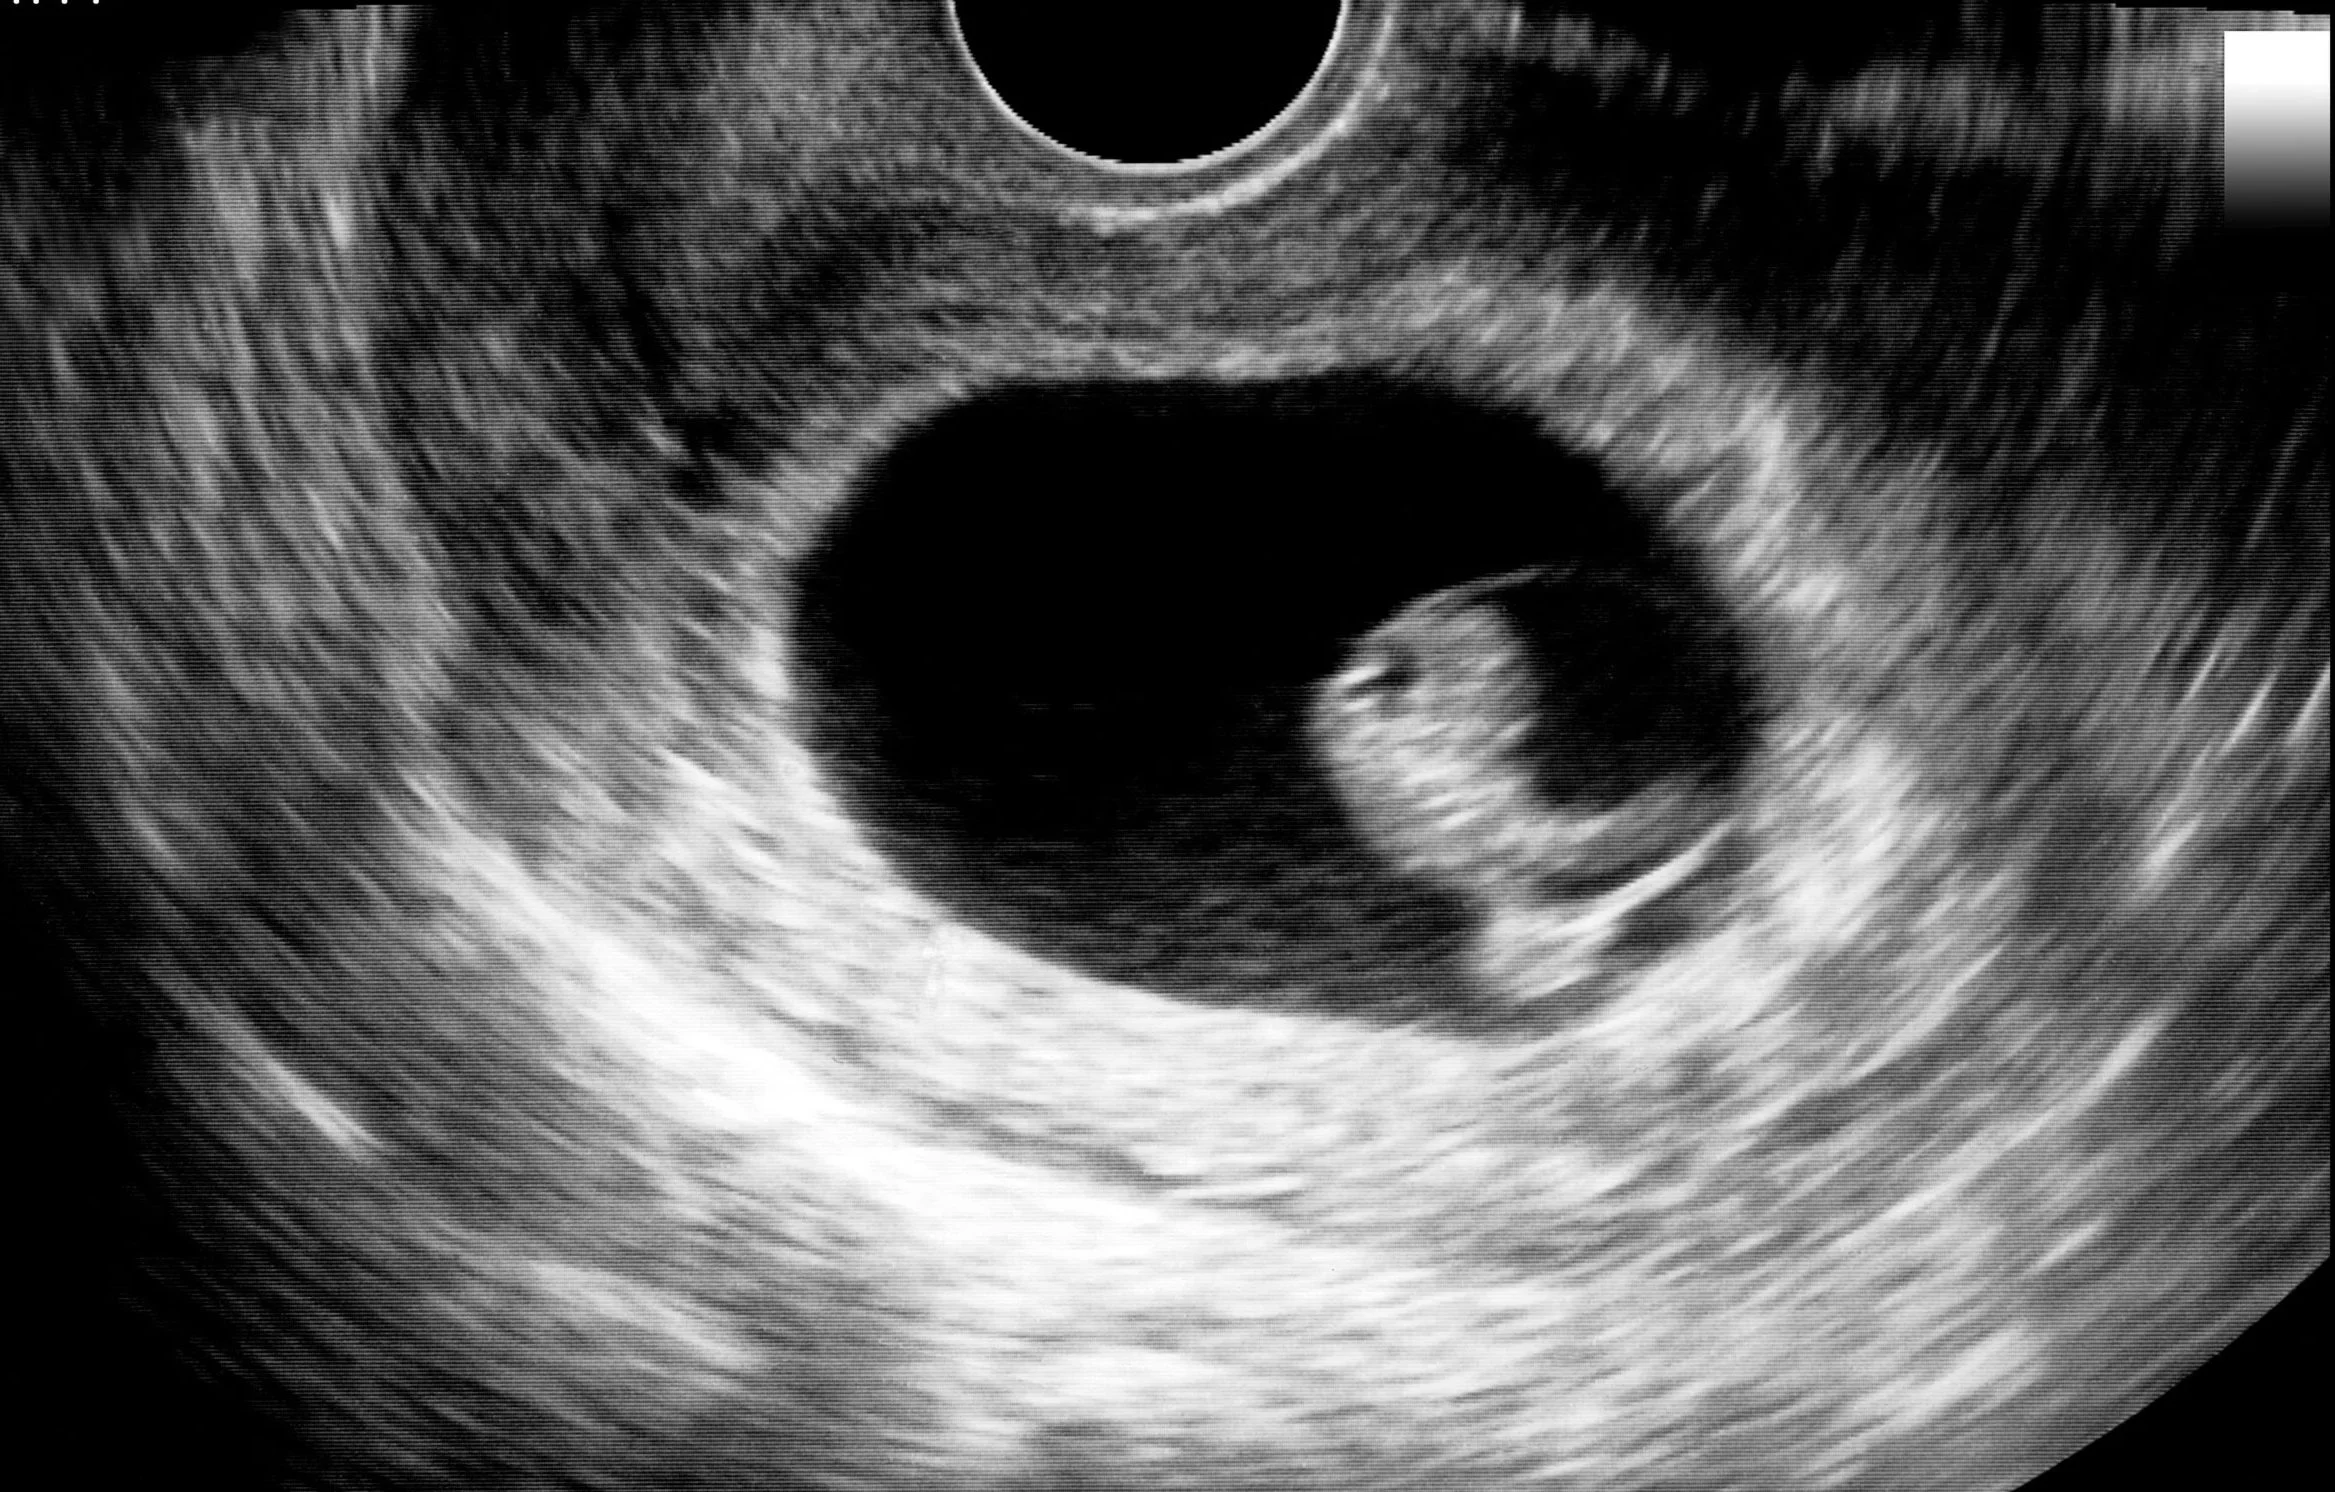

Termijnecho (rond 8–12 weken)

De termijnecho is vaak de eerste keer dat je je baby ziet. We kijken of je zwangerschap in de baarmoeder zit, hoeveel weken je zwanger bent, wat de definitieve uitgerekende datum wordt en of er één of meerdere baby’s zijn.